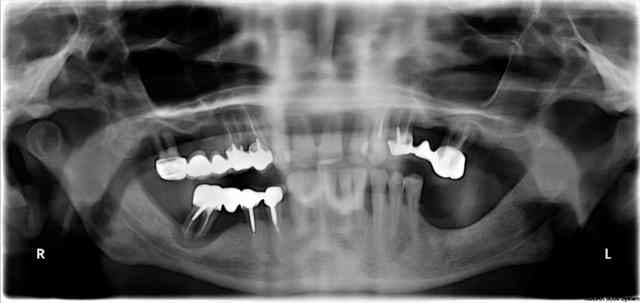

projet prothétique réhabilitation complète implanto porté en MCI, la S.I.A.O permet d'objectivé la faisabilité

-prothèse métallique présent lors du scanner

-mobilité trop importante pour prendre une empreinte du maxillaire

Résultat clinique de la MCI en 1 temps chirurgical

La photo est prise à 24h de l'intervention la pano à 2 mois